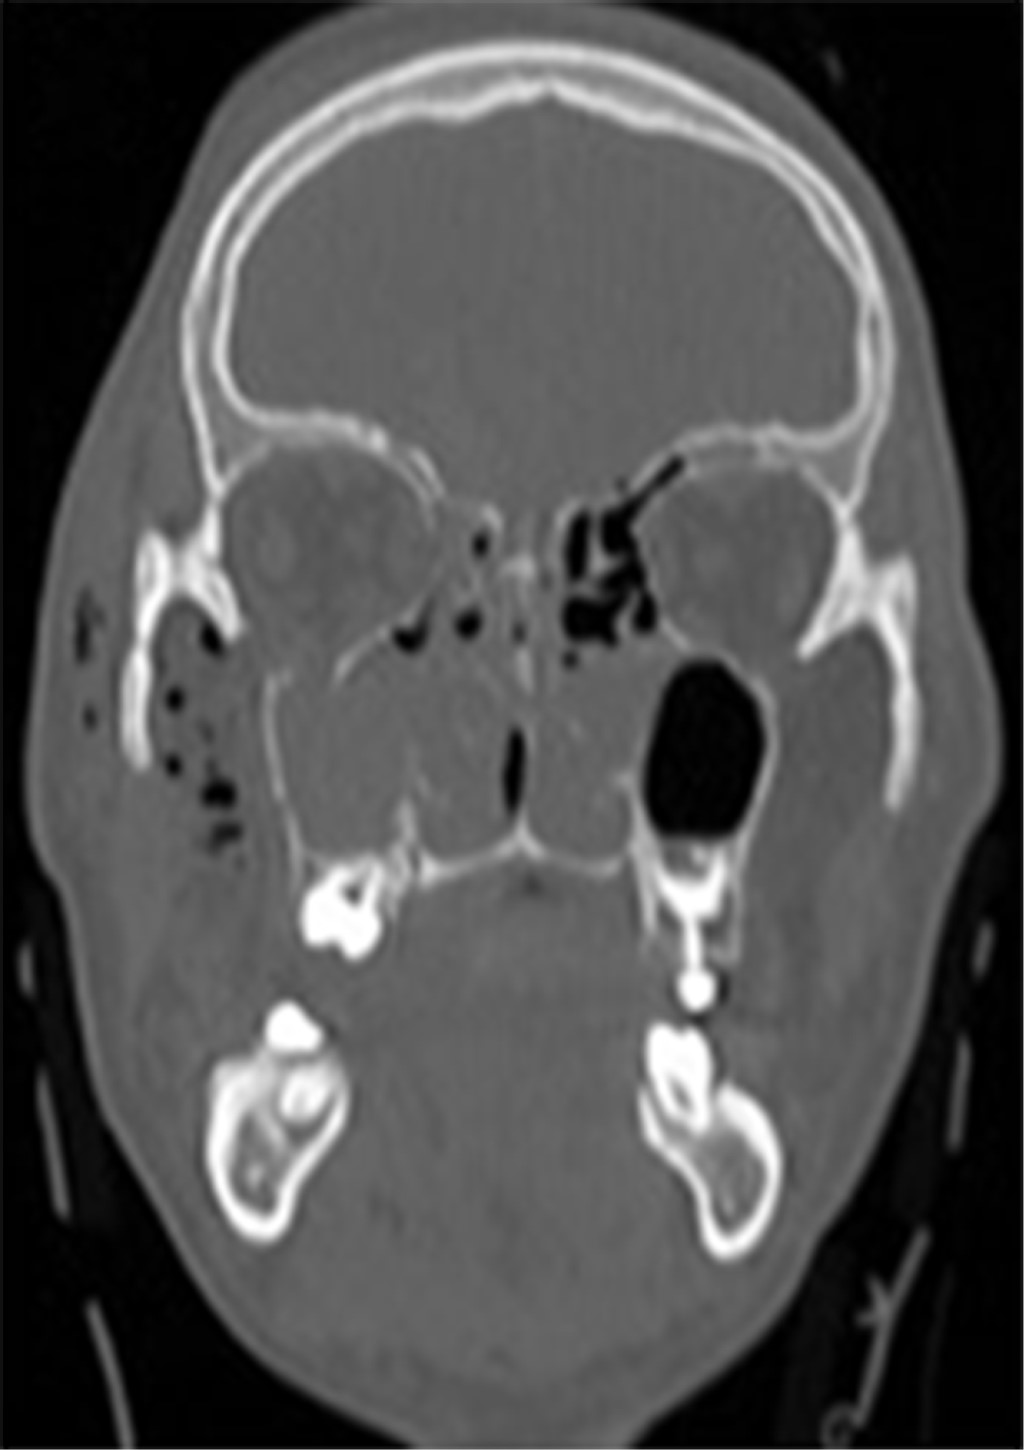

La tomografía computarizada coronal de la cara muestra una extensa destrucción de la pared orbital medial (Figura 5) y la reconstrucción con malla de titanio para corregir el extenso defecto (Figura 6).

Bajo anestesia general, se realizó un acceso bicoronal e infraciliar para la extracción de tejidos blandos y la reducción de la fractura de la pared medial así como la reconstrucción con malla orbital premoldeada, devolviendo el marco y el volumen orbitario. Una tomografía de la cara en el postoperatorio inmediato mostró la reconstrucción de la órbita con malla y tornillo del sistema de fijación de 1.5 mm (Figuras 7 y 8). A continuación, se realizó una prueba de ducción forzada con fórceps Adson y se comprobó la movilidad pasiva del globo. Seguimiento de 60 días en el postoperatorio, sin presentar restricciones de movimiento ocular, distopía y diplopía, con retorno de la agudeza visual, y edema discreto en región periorbitaria.